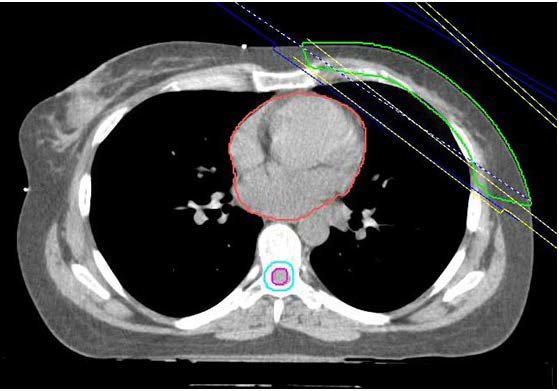

Figure 2: Planning CT scan indicating the area irradiated in DIBH (ABC).